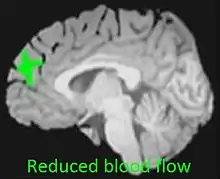

Reduced blood flow in prefrontal cortex of adolescent cannabis users[1]

The endocannabinoid system is directly involved in adolescent brain development.[22] Adolescent cannabis users are therefore particularly vulnerable to the potential adverse effects of cannabis use.[22] Adolescent cannabis use is associated with increased cannabis misuse as an adult, issues with memory and concentration, long-term cognitive complications, and poor psychiatric outcomes including social anxiety, suicidality and addiction.[23][24][25]